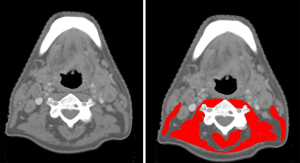

Muscle tissue was identified using Hounsfield Unit (HU) range settings from −29 to +150 HU, which is specific for muscle tissue. Muscle tissue was delineated at the level of the third cervical vertebra (C3). The SMA was defined as the pixel area within the delineated area with a radiodensity between −29 and +150 HU (23). Delineation of muscle tissue was manually performed using the Slice-O-matic software v 5.0. Muscle tissue delineation at the level of C3 was performed by selecting the first slide showing both transverse processes and the entire vertebral arc when scrolling from caudal to cranial direction. The contours of the paravertebral muscles and both sternocleidomastoid muscles were manually traced. The SMA at the level of C3 was calculated as the sum of the paravertebral muscle and both sternocleidomastoid muscles. If evident lymph node metastasis hindered accurate delineation of one sternocleidomastoid muscle, the SMA of the contralateral sternocleidomastoid muscle was used as an estimation of the SMA of the affected sternocleidomastoid muscle. After delineation, SMA was automatically retrieved from Slice-O-matic. For MRI, muscle area was manually segmented, and fatty tissue was manually excluded. The overall intraclass correlation coefficient (ICC) for the muscle SMA obtained by CT and MRI has shown to be excellent (ICC 0.9, P<0.01) (24), and can therefore be used interchangeably for measuring CSA at the level of C3. The cervical SMI (CSMI) was calculated by dividing the SMA at the level of C3 by the squared height of the patient. Figure 2 shows muscle tissue delineation at the level of C3.